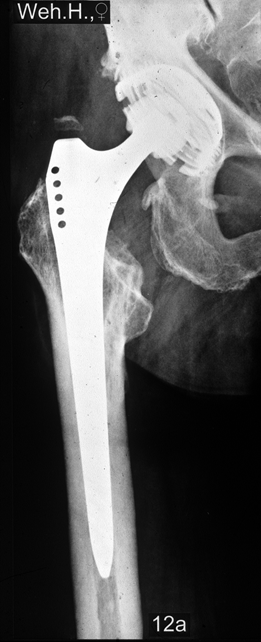

Fallbeispiel

Weiblich, 78 Jahre. Die

Bilder zeigen eine deutlich gelockerte zementierte

Hüftprothese. Der Knochen um den Zement ist stellenweiße

papierdünn

Zustand nach Austausch der

zementierten Prothese durch eine Bicon-Pfanne sowie

einen SLR-Schaft.

Die Röntgenbilder zeigen das Ergebniss nach 13 Jahren.

Die nun 91 jährige Patientin ist gut gehfähig und völlig

beschwerdefrei.

|

Zustand nach Austausch beider Komponenten durch

eine Bicon-Pfanne sowie einen SLR-Schaft.

Röntgen 12 Jahre nach der Austauschoperation

sind Schaft und Pfanne stabil eingebaut. Die Patientin ist völlig beschwerdefrei und unbegrenzt gehfähig.